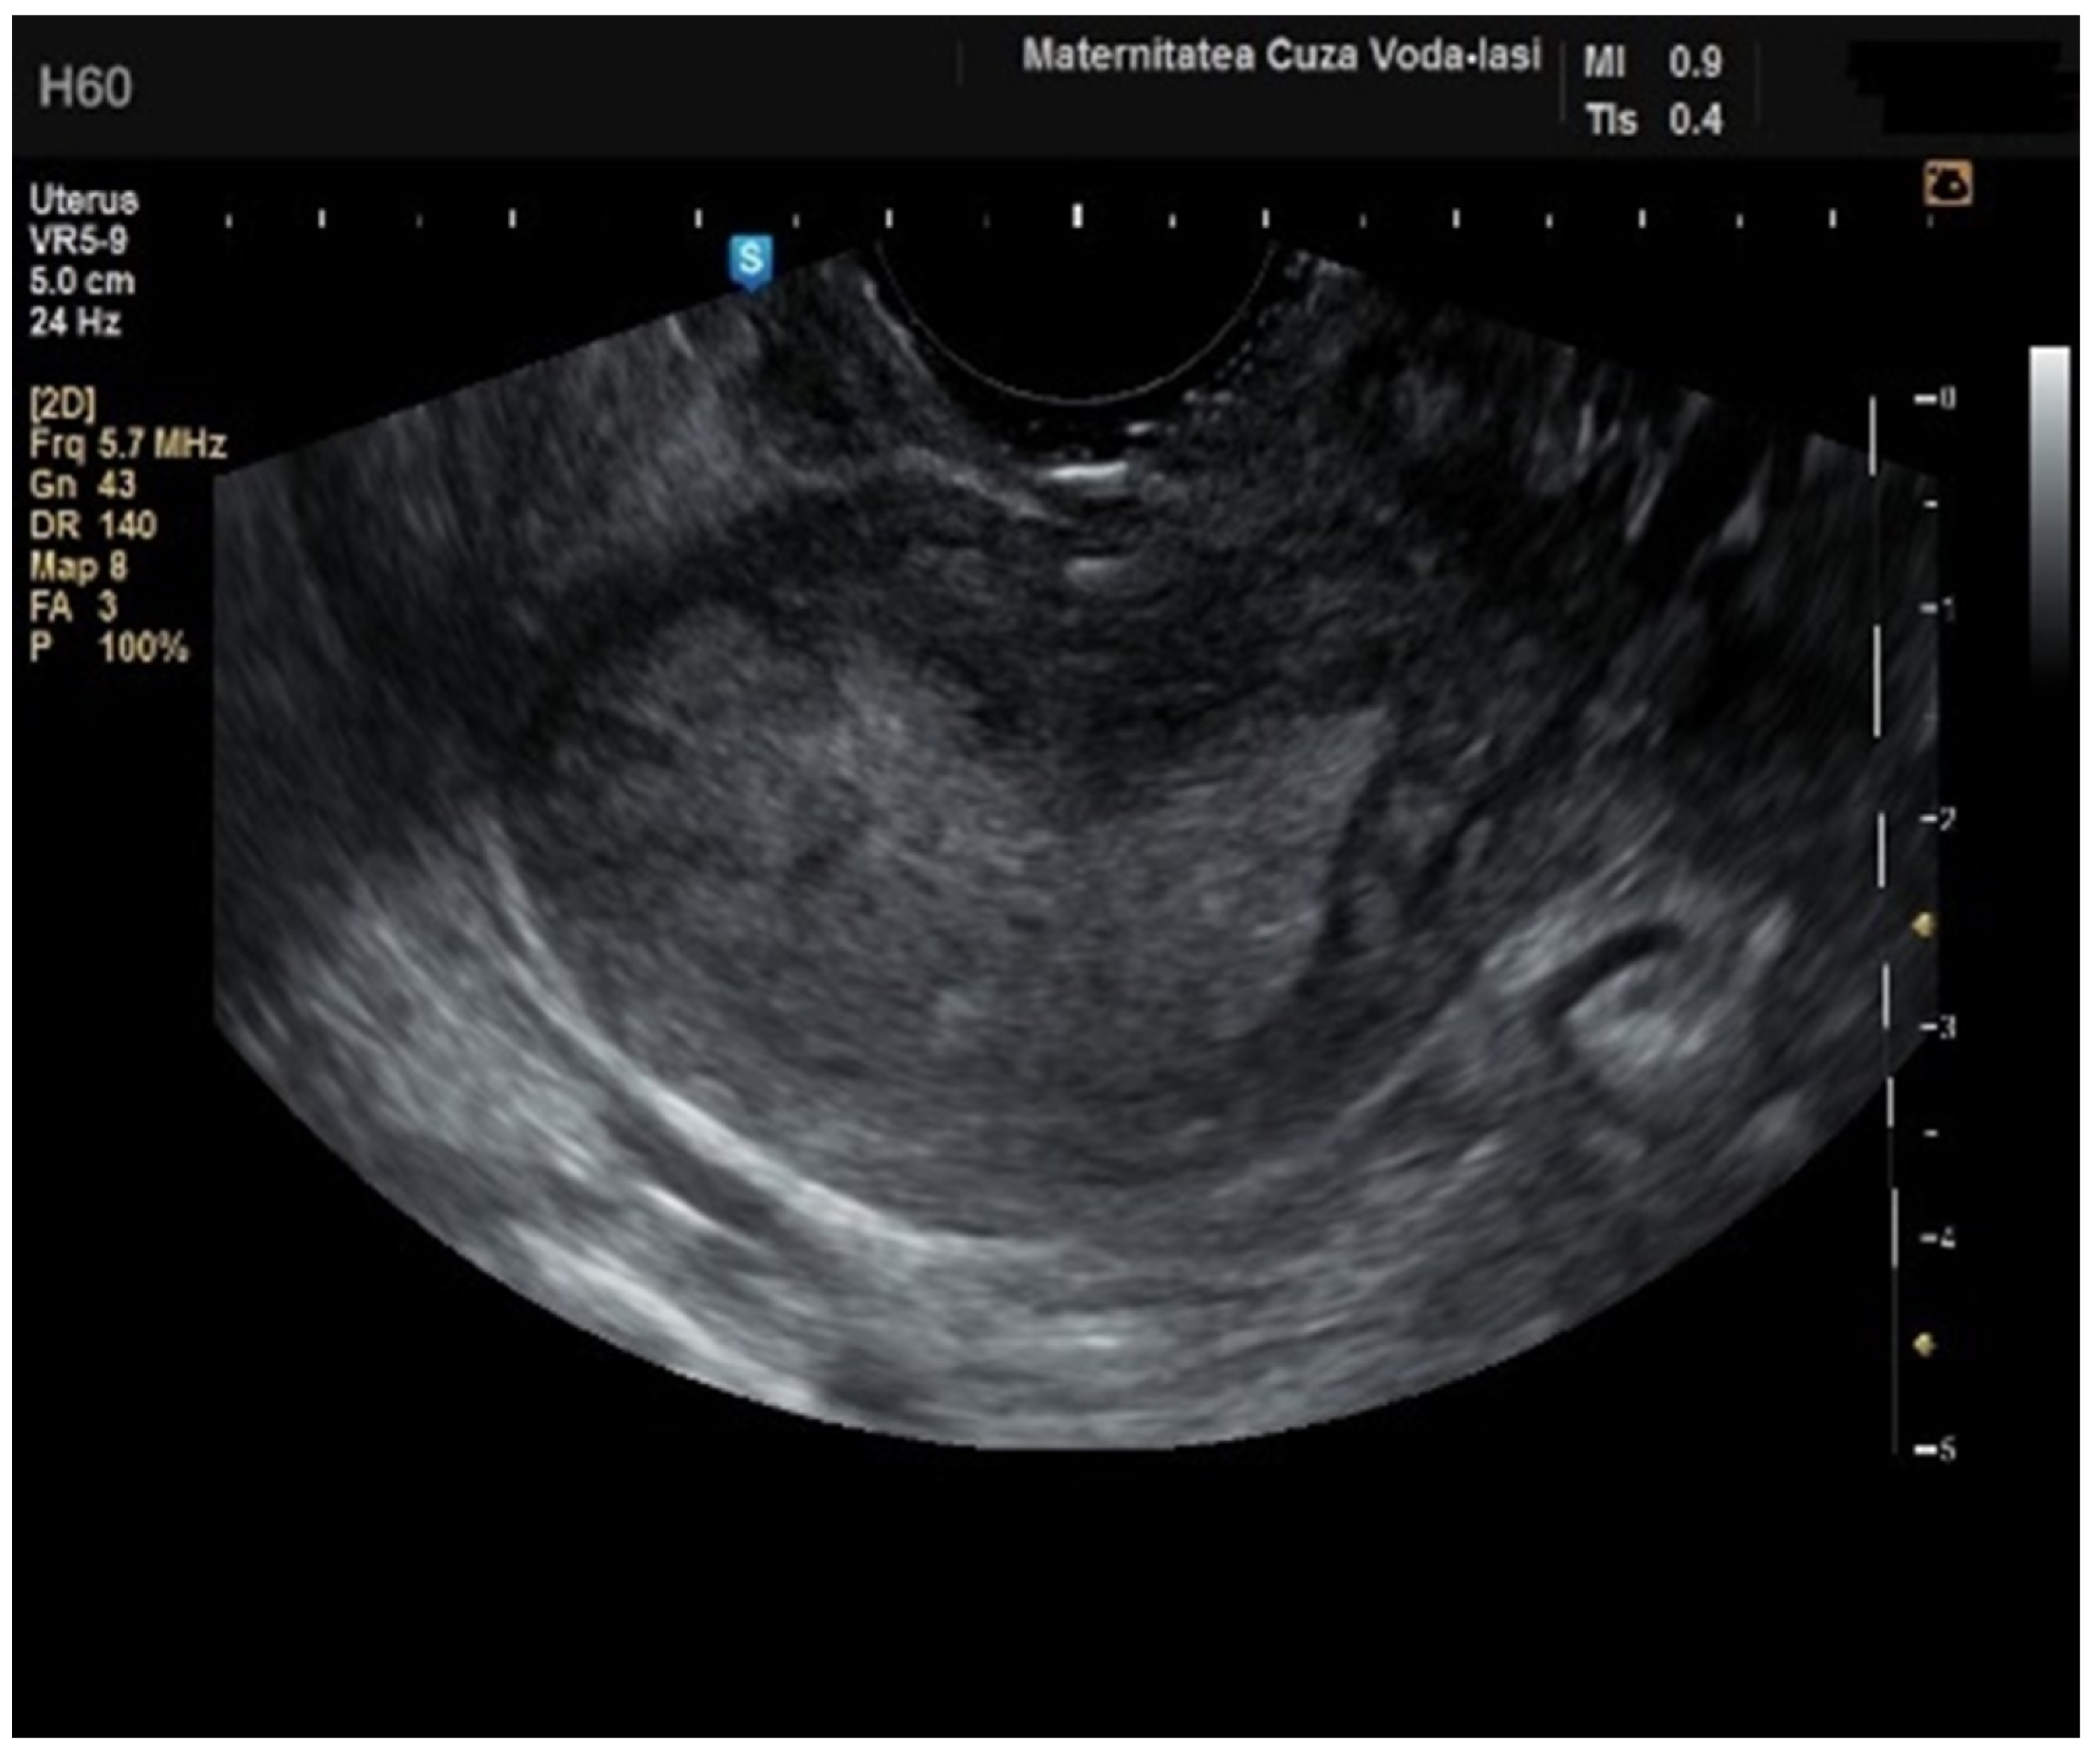

Figure 2. Ultrasonographic imaging of endometrial cancer.

The average endometrial thickness, as measured by transvaginal ultrasonography, was found to be 18.02 ± 10.94 mm (range: 5–64 mm). Malignancy was identified in 22.84% of cases with uterine cavity findings. The mean endometrial thickness for women diagnosed with endometrial cancer was 24.49 ± 13.33 mm (95% confidence interval [CI]: 14.34 to 35.16), (Figure 2), whereas those with other pathologies had a mean thickness of 16.10 ± 9.37 (95% CI: 13.14 to 18.57), (Figure 3), with statistical significance (p = 0.028). When endometrial thickness was used as a standalone variable to build a model for estimating the risk for endometrial malignancy it demonstrated the highest AUC with a value of 0.682 (95% CI: 0.452–0.912). A cut-off threshold of 26 mm for endometrial thickness yielded a sensitivity of 62.5% and a specificity of 89% (Figure 4).